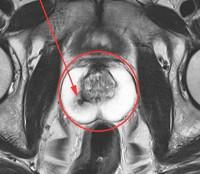

На наличие злокачественной опухоли предстательной железы указывает сигнал низкой интенсивности в области неоплазии с сигналом высокой интенсивности от окружающих здоровых тканей на T1-взвешенных изображениях. С помощью МРТ предстательной железы вы можете определить точное местоположение, распространенность и направление роста опухоли. На основании степени накопления и удаления контрастного вещества можно оценить степень злокачественности опухоли. Кроме того, МРТ предстательной железы дает возможность обнаружить факт сверхорганизованного распространения опухоли, повреждения лимфатических узлов и прилегающих костных структур. При железистых аденомах на МРТ предстательной железы гиперинтенсивные тени видны в области гиперплазии, а стромальные - с гипоинтенсивными тенями. При простатитах конусообразных, гипоинтенсивных участков с четкими контурами не обнаружено, массового эффекта нет.